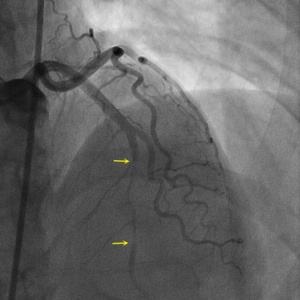

SCAD Angiography

Shown below are animated and static angiography images exemplifying each type of SCAD. For additional angiographic images of SCAD, click here.

Type 2A

Projection angle: 5 LAO, 34 CRA. Type 2A SCAD is seen in L3.